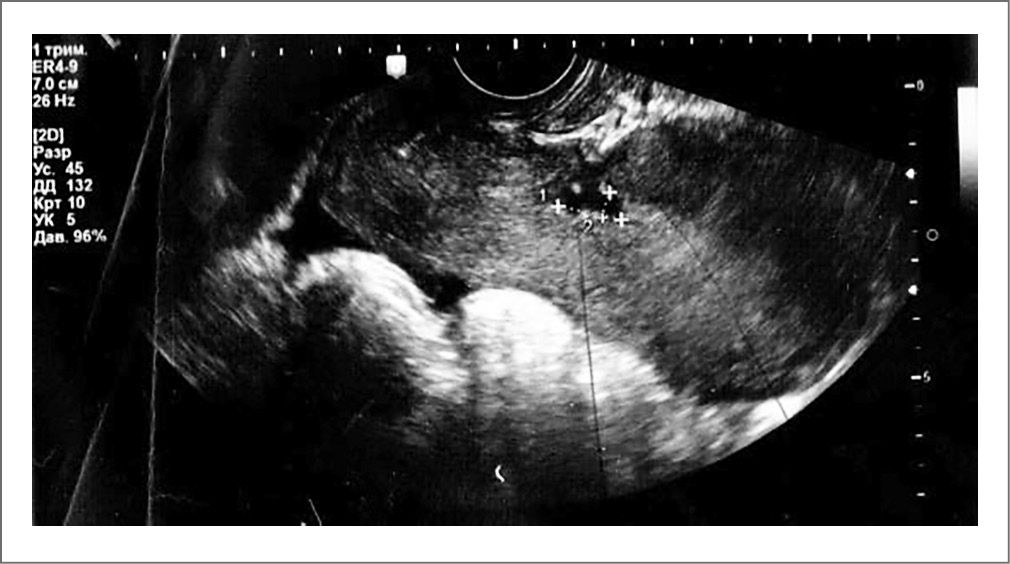

По данным ультразвукового исследования органов малого таза матка имела размеры, соответствующие 8 нед беременности, с ровными наружными контурами. В несколько расширенной полости матки и цервикального канала диагностированы гиперэхогенные включения с акустической тенью. В области послеоперационного шва обнаружены жидкостные включения до 16 мм в диаметре (рис. 2). Уровень жидкости за маткой составлял 4 мм.

Рис. 2. Ультразвуковое исследование органов малого таза (жидкостные включения в области послеоперационного шва на матке).